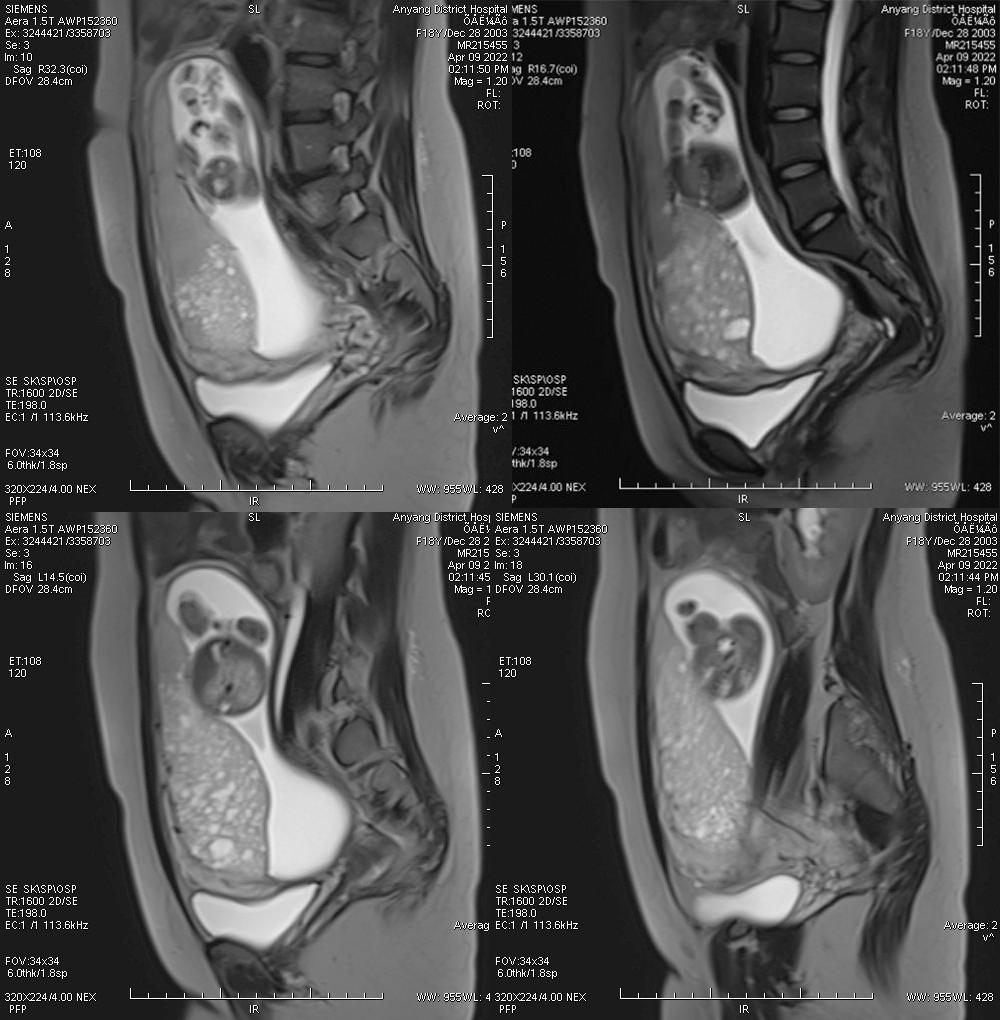

病例二

女,30 岁,侵蚀性葡萄胎,穿透宫壁全层。引道出血 20 多天,既往有 3 次人工流产病史。